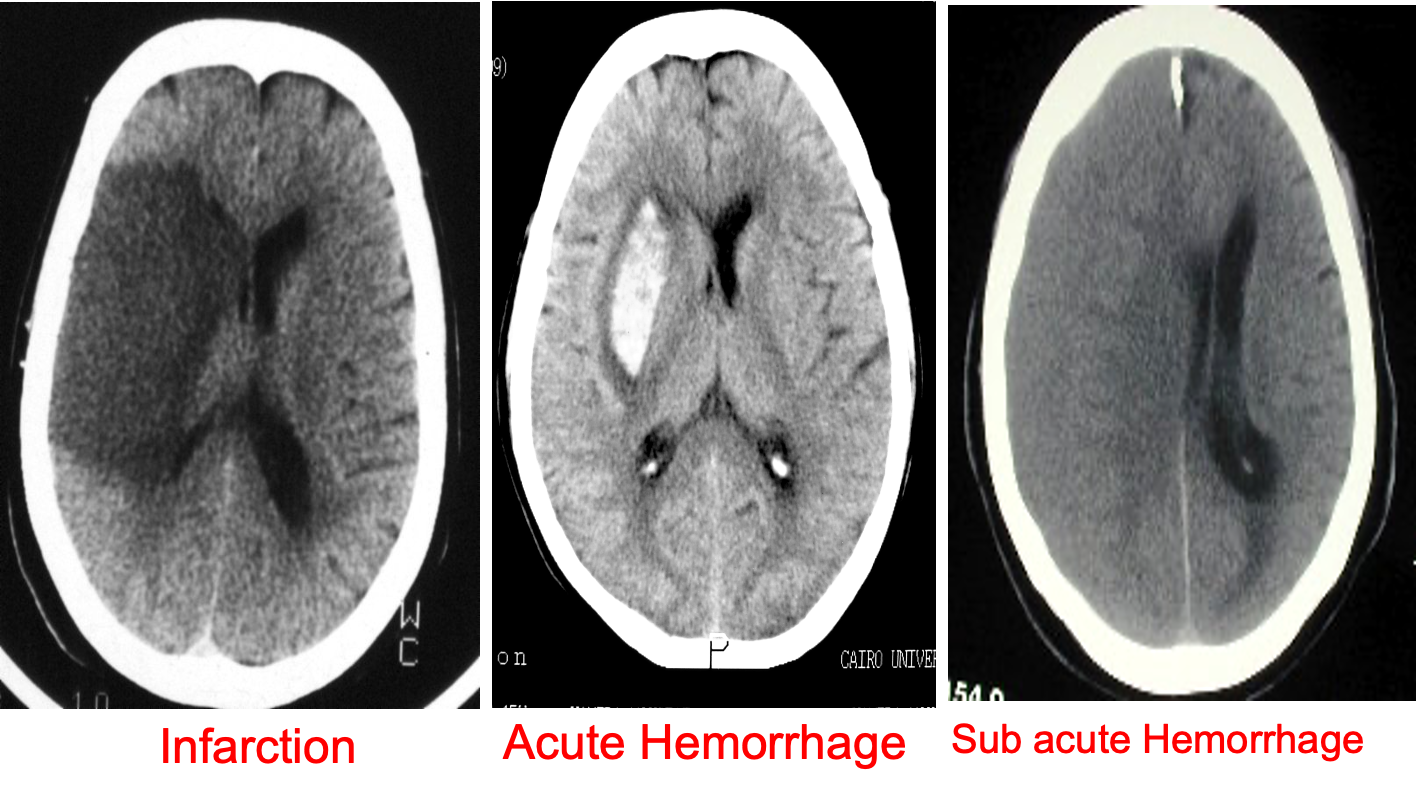

Pattern of enhancement

- Homogenous

- Heterogeneous

- Ring

- Serpiginous; arteriovenous malformation [AVM]